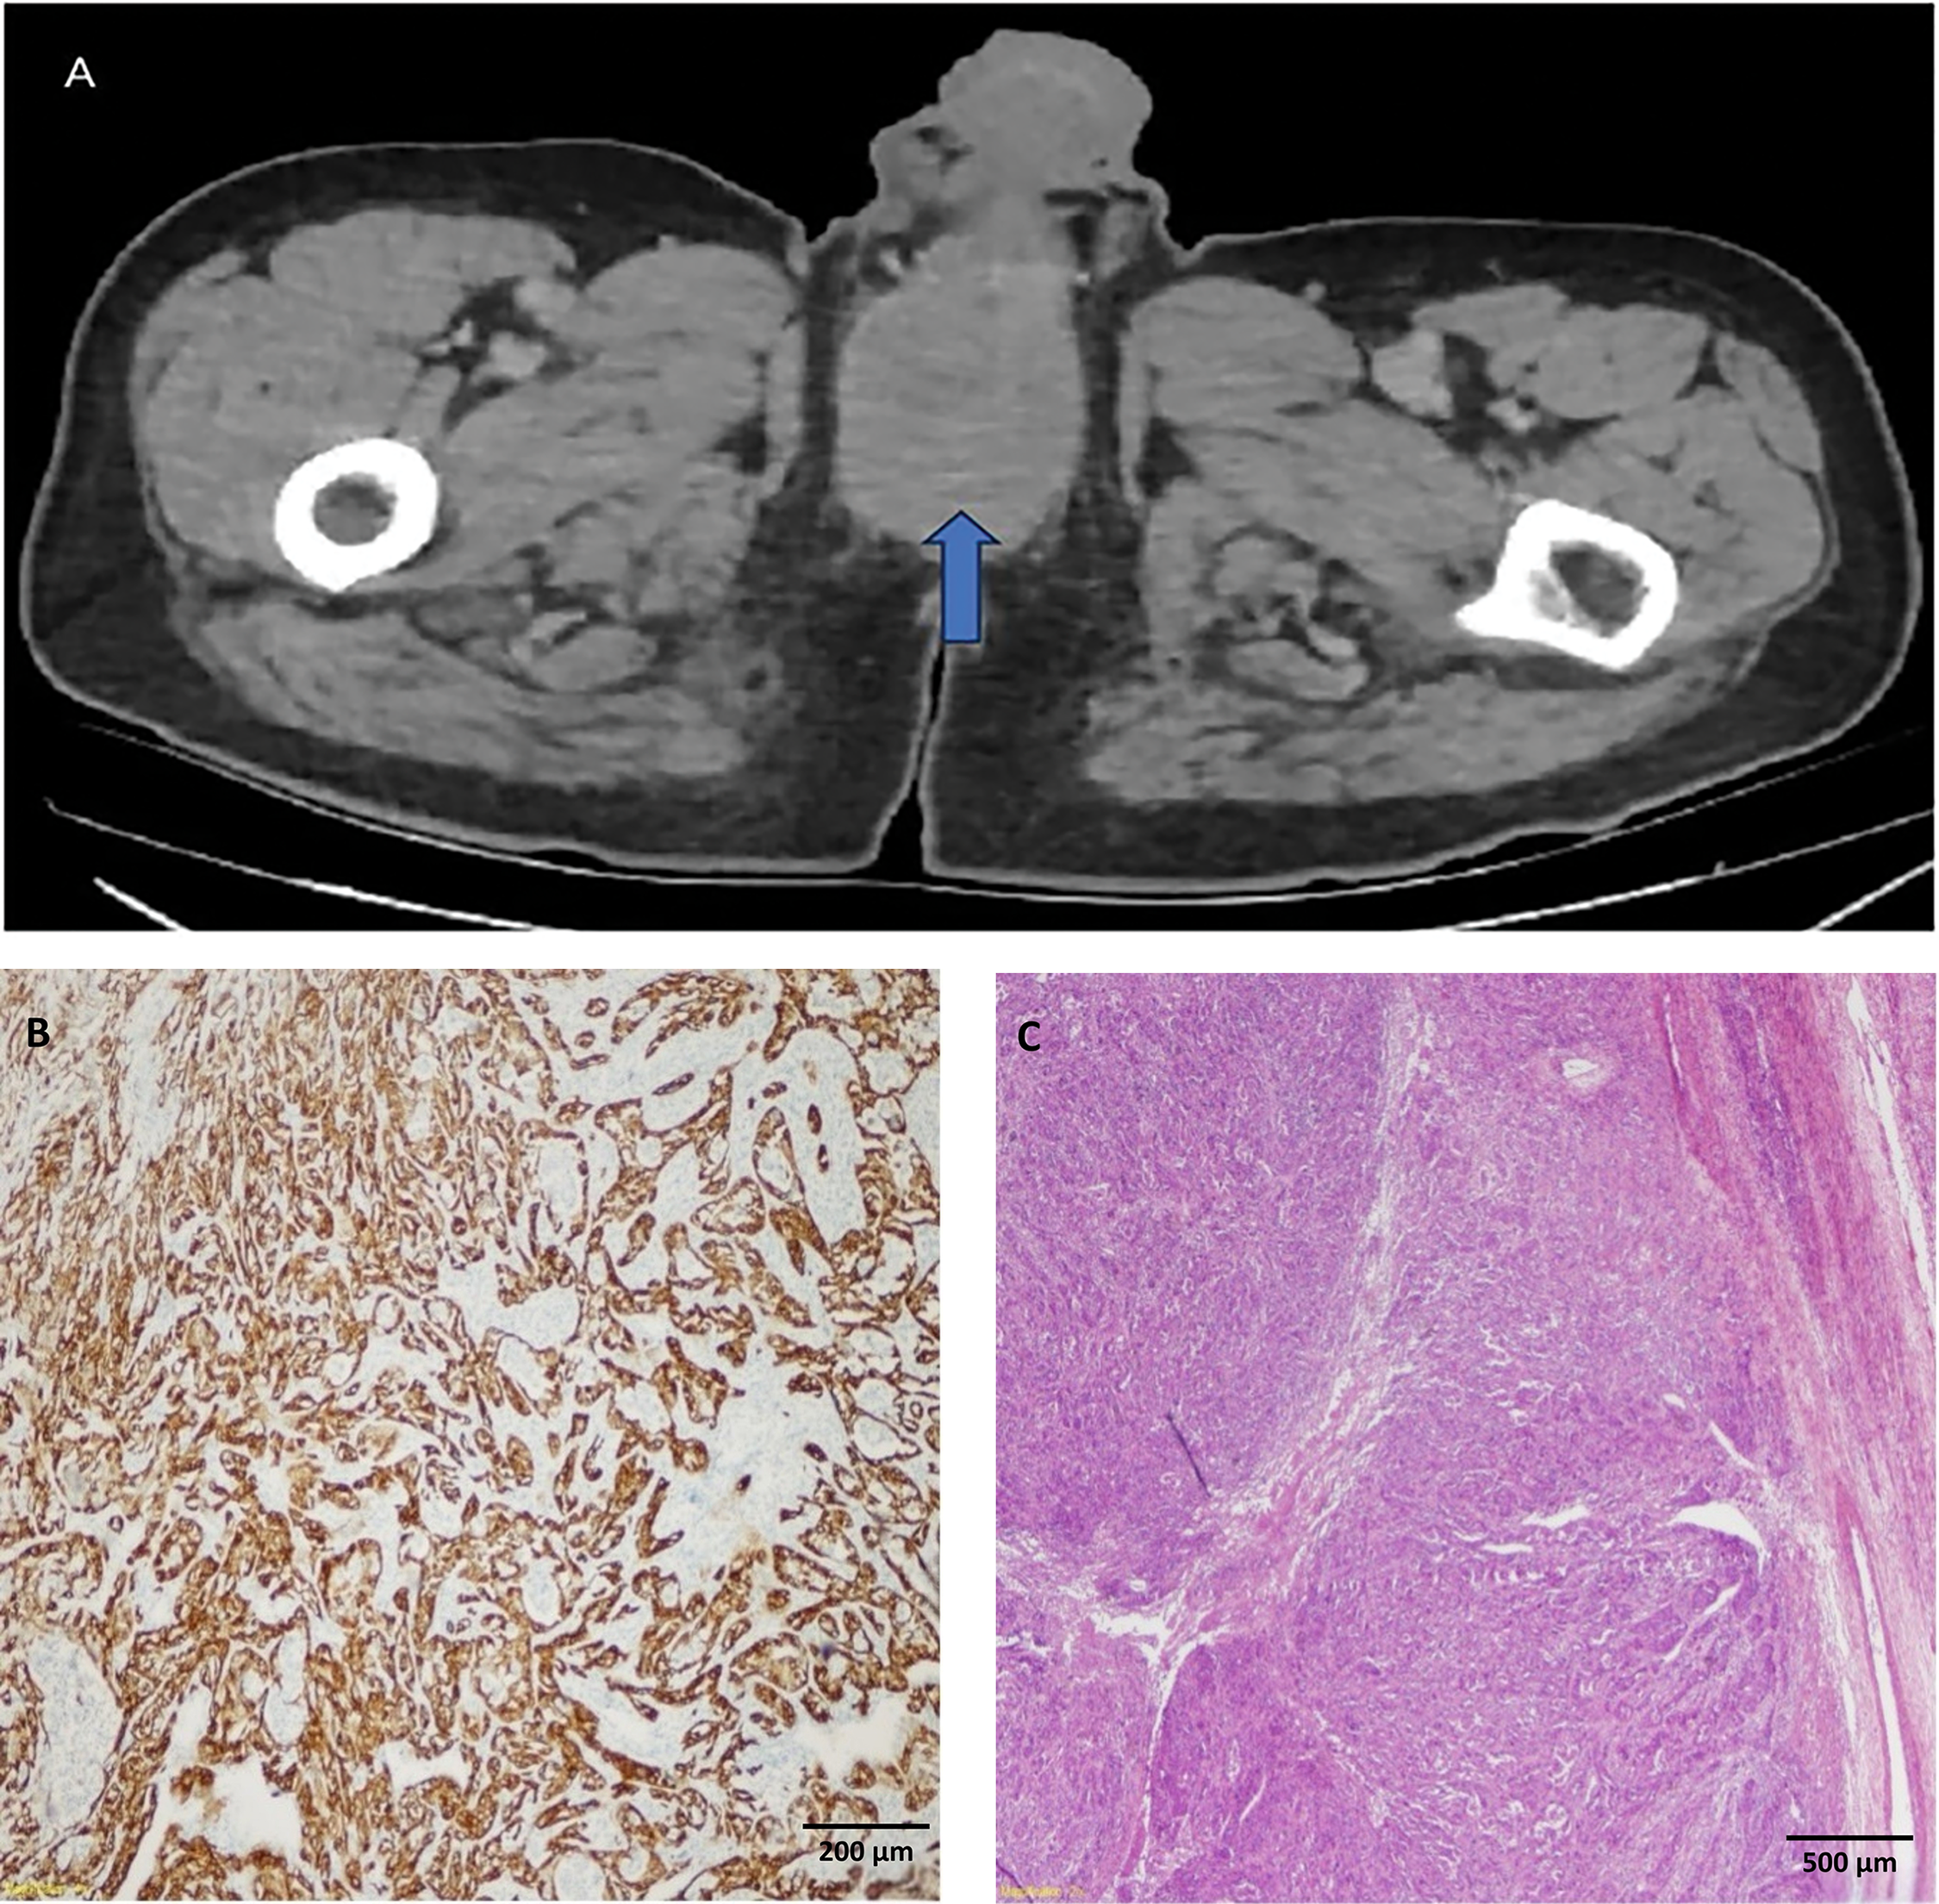

Following incomplete resection of recurrent bladder tumors, he underwent radical cystoprostatectomy and extended lymphadenectomy. At three-year follow-up, PET-CT revealed a metastatic lesion at the right 2th proximal interphalangeal (PIP) joint. Surgical excision confirmed metastatic urothelial carcinoma (Figure 2).

FIGURE 2. Histological and macroscopic images of finger metastasis. (A) Tumor cells with eosinophilic cytoplasm and thin fibrous septa in between, showing a poorly differentiated appearance (hematoxylin-eosin [H&E] staining, 20×) finger metastasis. (B) Macroscopic view of finger metastasis second proximal interphalangeal (PIP) (shown with blue arrow)

A bladder urothelial carcinoma metastasizing to the hand, represents an acrometastasis to the distal extremity. Such occurrences are exceedingly rare, comprising only ~0.1% of all bone metastases.13,14 In a systematic review of hand metastases, the majority originated from lung cancers, with genitourinary tumors accounting for a smaller fraction.6 Acrometastases most often affect the distal phalanges (about 21% of cases), followed by metacarpals (16%) and proximal phalanges (7%).13,14 Metastatic carcinoma to the digits of the hand has been noted only in isolated reports and is often a harbinger of advanced disease.13 Once diagnosed, surgical excision (metastasectomy) can provide symptom relief and local disease control, although the development of an acrometastasis generally signifies aggressive systemic disease.